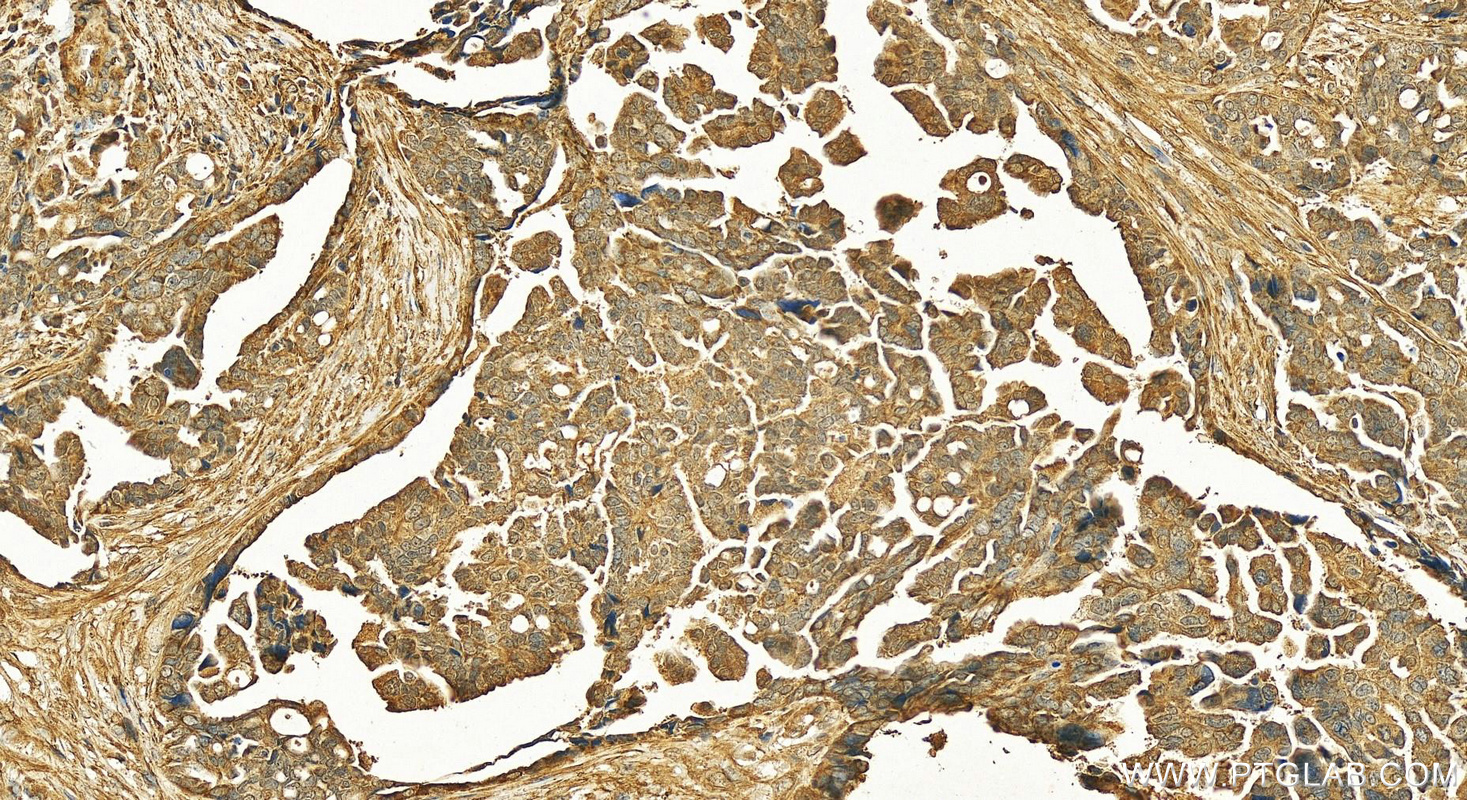

| Positive IHC detected in | human ovary cancer tissue, human kidney tissue, human liver tissue, human ovary tissue, human skin tissue, rat ovary tissue Note: suggested antigen retrieval with TE buffer pH 9.0; (*) Alternatively, antigen retrieval may be performed with citrate buffer pH 6.0 |

| Immunohistochemistry (IHC) | IHC : 1:50-1:500 |